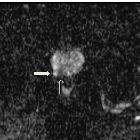

Neurofibromas are benign peripheral nerve sheath tumors usually solitary and sporadic, however, there is a strong association with neurofibromatosis type 1 (NF1). These tumors present as a well-defined hypodense mass with minimal or no contrast enhancement on CT. On MRI, they usually are T1 hypointense and T2 hyperintense with heterogeneous contrast enhancement.

MRI

- T1: hypointense

- T2

- hyperintense

- target sign

- a hyperintense rim and central area of a low signal may be seen

- this is thought to be due to a dense central area of collagenous stroma

- although this sign is highly suggestive of neurofibroma, it is occasionally also seen in schwannomas and malignant peripheral nerve sheath tumors

- fascicular sign

- T1 C+ (Gd): heterogeneous enhancement